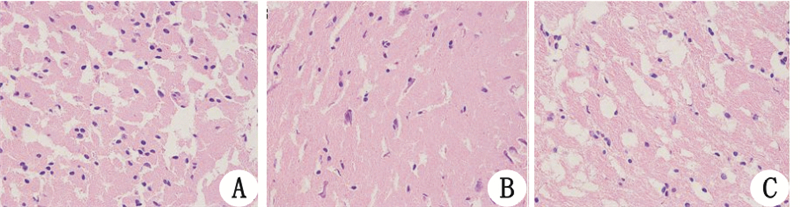

PCAS组均可见脑组织出现细胞肿胀,胞浆嗜酸性变,胞核碎裂、溶解、固缩,淋巴细胞和中性粒细胞浸润(图 1B)。PAR-1阻断剂组脑组织上述变化较轻(图 1C)。假手术组未见异常变化(图 1A)。

| A:sham组;B:PCAS组;C:PAR-1阻断剂组 图 1 海马组织HE染色结果(×400) |

本研究利用PAR-1阻断剂SCH79797干预兔 PCAS模型,结果发现SCH79797能明显降低PCAS兔血清神经元特异性烯醇化酶(NSE),而NSE是反映神经元早期损伤特异的指标。海马组织HE染色分析表明,PCAS发生72 h脑组织仍然出现细胞肿胀,胞浆嗜酸性变,胞核碎裂、溶解,炎性细胞浸润,而PAR-1阻断剂组脑细胞变性、坏死及炎性细胞浸润明显减轻。由此可见,PAR-1阻断剂SCH79797能明显减轻心肺复苏后神经元损伤。